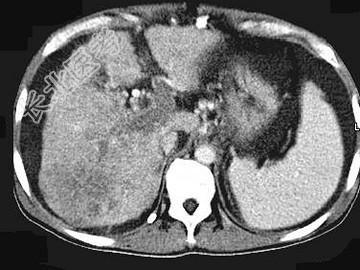

- 单项选择题女,50岁, 曾患乙型肝炎,肝硬化多年, 右上腹胀痛1月余,CT检查如图所示, 最可能的诊断为 ( )

A、肝硬化、腹水伴胆管细胞癌

B、肝硬化、腹水伴原发性肝癌

C、肝硬化、腹水、肝癌并门脉癌栓

D、肝硬化、腹水并肝脓肿

E、肝硬化、腹水并肝血管瘤